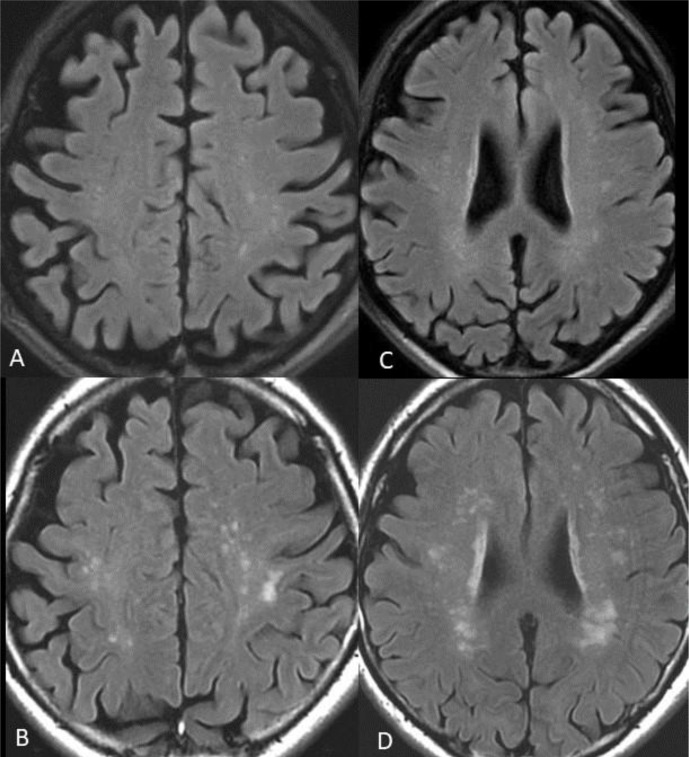

MRI findings

Twenty-five patients (71%) showed multiple subcortical white matter lesions, located in the cerebral hemispheres near the grey-white matter junction, particularly in the frontal and parietal lobes. Six patients had had MRI performed in the acute phase during their hospitalisation, and all of these patients had additional white matter lesions at the follow-up MRI. Figure 2 shows an example of a patient with new white matter lesions at follow-up, with a typical distribution.

Figure 2.

T2-FLAIR images of one of the patients. (A) and (C), superior row, are from the MRI examination performed during the acute phase. (B) and (D), inferior row, are from the MRI examination at late follow-up. New white matter lesions appear at the follow-up MRI, with a typical distribution with a predilection for the parietal and frontal lobes. T2-FLAIR, T2-Fluid Attenuated Inversion Recovery.

Seven of the patients with pathological MRI had confluent white matter lesions, with a propensity for a biparietal distribution, whereas eight patients had abnormalities on the SWI, mostly located subcortically, near the grey-white matter junction. Figure 3 shows an example of the SWI pattern in one of the patients. The MRI findings are summarised in online supplementary table 2.

This study presents brain MRI and neurocognitive findings, as well as self-reported fatigue at long-term follow-up after COVID-19 hospitalisation in patients with clinical risk indicators of higher cerebral dysfunction. The main radiological finding was the presence of multiple white matter lesions with a frontal and parietal distribution. This is in line with previous findings on MRI performed during the acute phase of COVID-19, where lesions associated with microvascular structures in the white matter have been reported.5 White matter lesions are often found with increasing age and can be a marker of cerebrovascular disease. In the present study, the group with abnormal MRI were older, which might be a partial explanation for white matter lesions being more frequent in that group. However, a meta-analysis of neurological complications associated with COVID-19 also found that cerebrovascular disease was the most common neurological injury in individuals aged >50 years, occurring in more than 50% of individuals, and could not be explained by increasing age.26 This suggests that there seems to be an age-associated vulnerability for cerebrovascular disease as a complication of COVID-19 infection. Furthermore, all the patients who underwent MRI during the acute phase of COVID-19 had acquired multiple new white matter lesions when examined at follow-up. This suggests that the COVID-19 infection might have an impact on the brain, even in the aftermath of the acute and subacute virus infection.